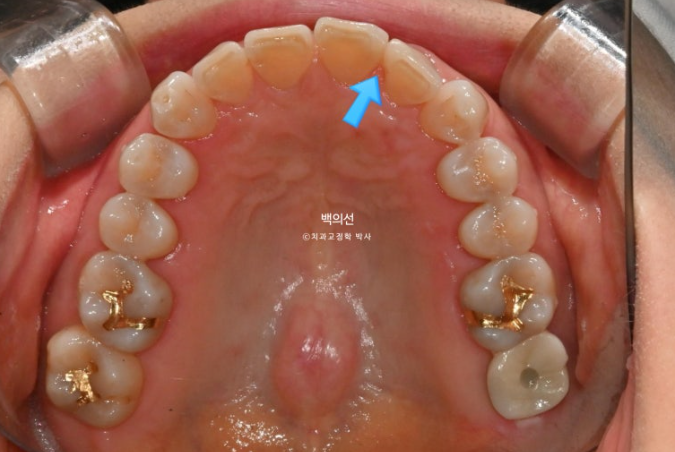

파란 화살표는 틈을 메워놓은 레진 입니다.

25.02

벌어진 틈을 메워놓는 레진을 제거한 모습입니다.

생각보다 틈이 꽤 크죠?

하지만 이 정도의 벌어짐, 틀어짐에는 인비절라인 익스프레스가 적절합니다.